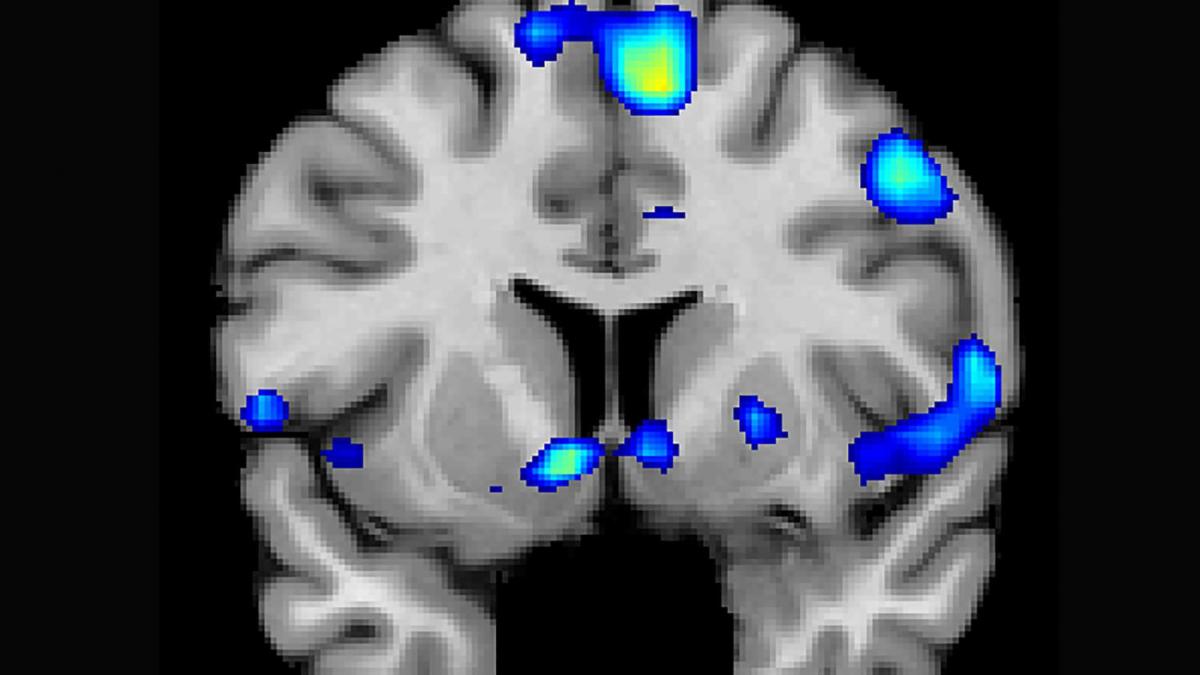

fMRI scans performed as the subjects underwent religious experiences. Credit: University of Utah Health Sciences

The active parts of the brain during religious experiences by the study participants, including a reward circuit, the nucleus accumbens. Credit: Jeffrey Anderson